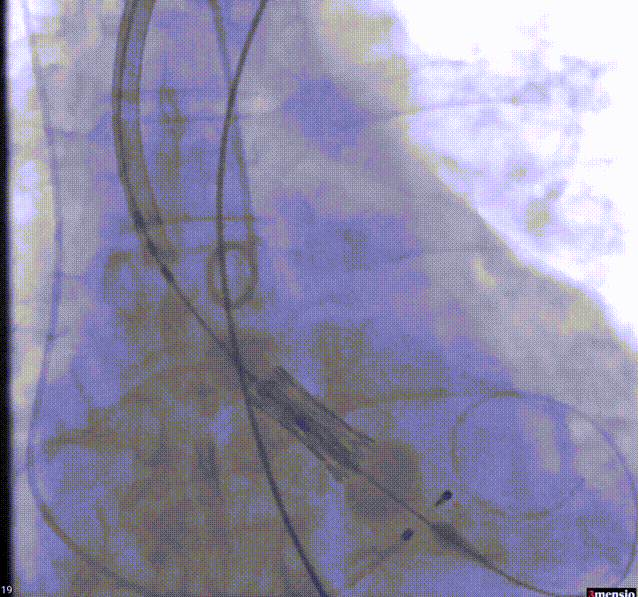

4.快速起搏下20mm球囊预扩;

球囊预扩